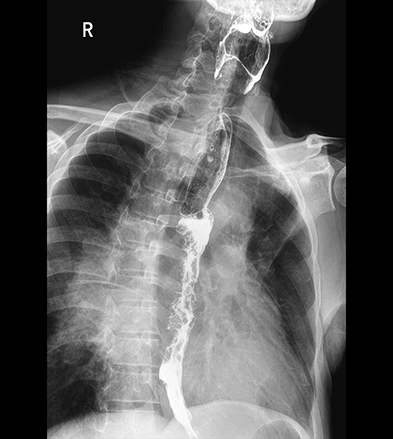

平板探测器

超大尺寸

超范围

超高像素

高清点片